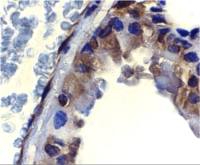

GSTM1 antibody detects GSTM1 protein at cytoplasm in rat heart by immunohistochemical analysis.

Sample: Paraffin-embedded rat heart.

GSTM1 antibody (GTX113448) diluted at 1:400.

Antigen Retrieval: Citrate buffer, pH 6.0, 15 min